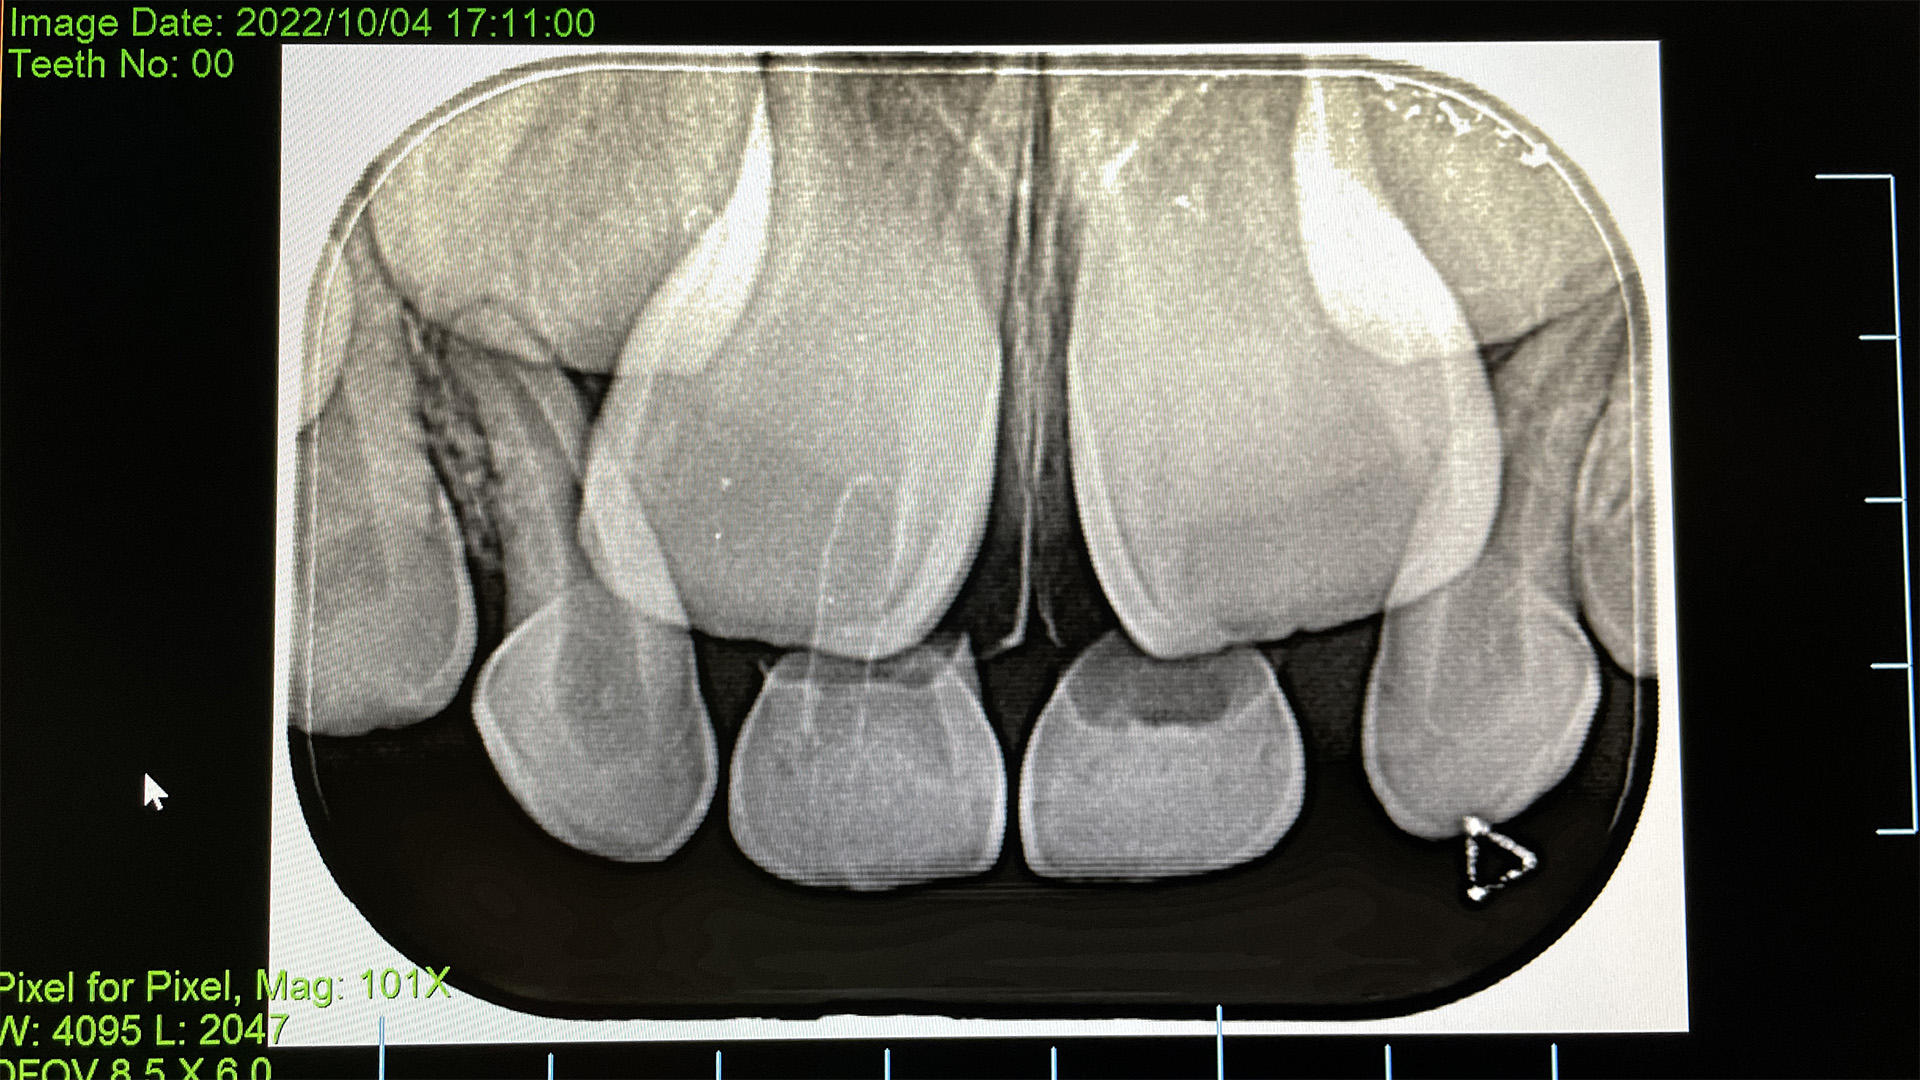

そしてレントゲンを歯医者で撮ってもらったと報告あり。

そこにはなんと、永久歯・しかもでっかいのが準備されている。

人間の体は謎だらけ。